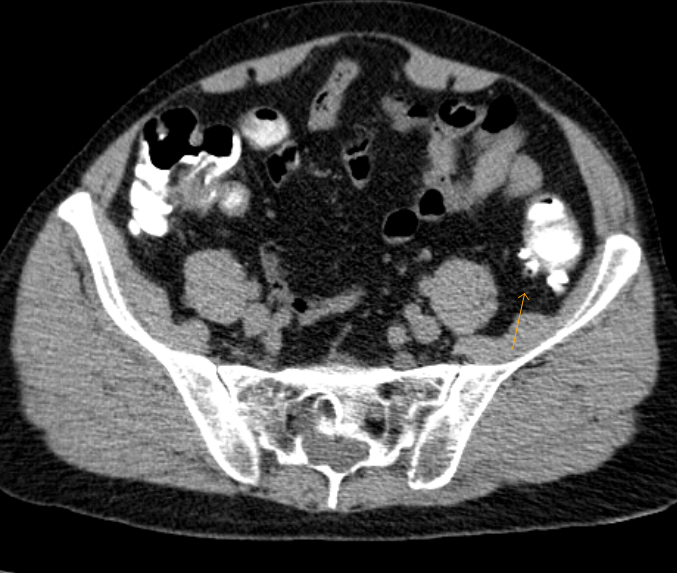

Diverticulitis. Axial CT image of a man with leftsided diverticulitis... Download Scientific Ct Scan For Diverticulitis A ct scan with contrast is the best test to diagnose it and guide treatment. diverticulitis is an infection or inflammation of small pouches in the colon wall. learn how to diagnose diverticulitis on abdominal ct scans by looking for thickened and enlarged. Find out the symptoms, complications, and differential diagnoses of diverticulitis. ct scan in a. Ct Scan For Diverticulitis.